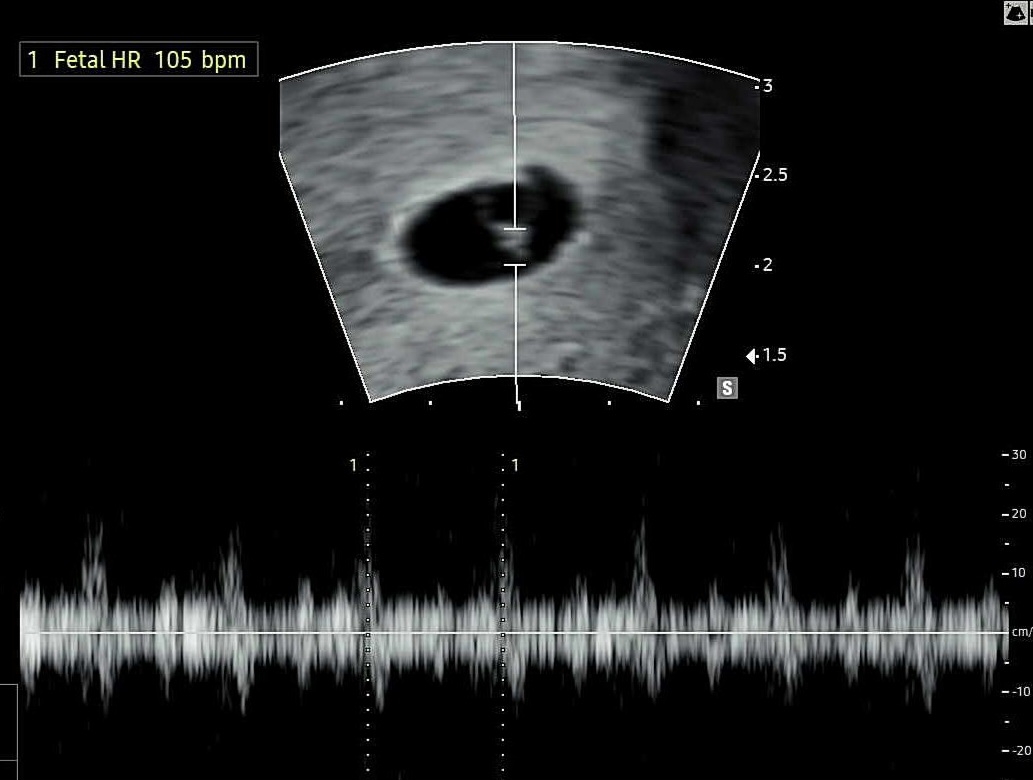

6주3일 심소듣고왔어요!

오늘 막생기준6주3일이고 정확한주수는 아기가 너무너무작아서 5일뒤 다시 병원 내원예정이예요 선홍빛냉이 살짝비춰져서 설연휴내내 걱정했는데 다행히 피고임없고 심장소리도 잘뛰어서 다행이예요ㅠㅠㅠㅠ